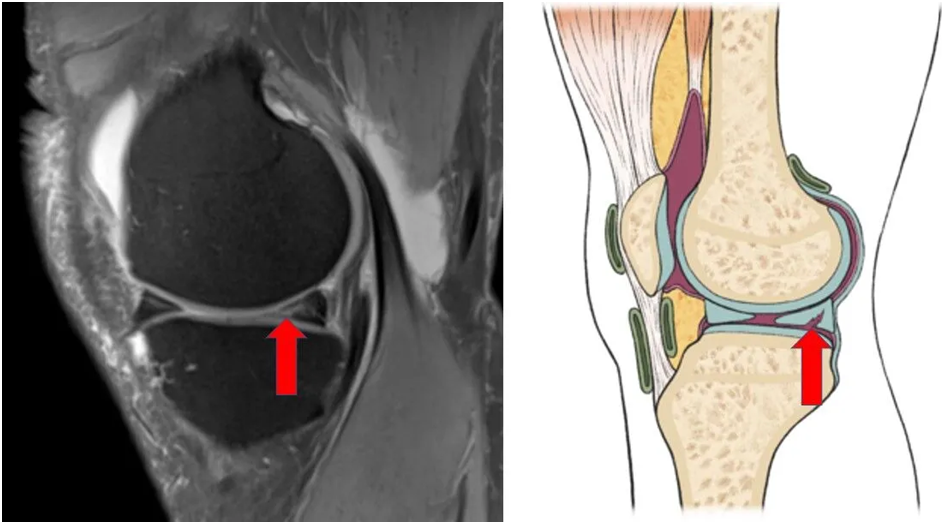

Meniscus tear repair surgery is a procedure used to repair a torn meniscus, a cartilage structure inside the knee joint. The meniscus acts as a cushion in the knee, helping to absorb shock and protect the joint. If torn, it can cause pain, swelling, and difficulty in movement.